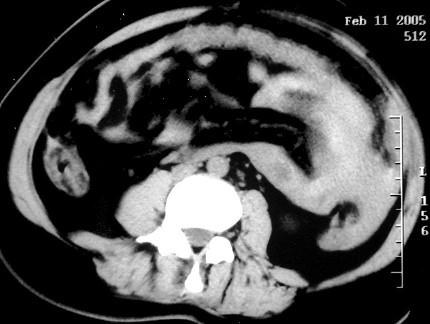

问题 女 ,32岁 ,因停经46天 ,少许不规则阴道流血15天 ,下腹胀痛 3 天入院,后穹窿穿剌抽出不凝血,CT检查如图所示,下列说法错误的是 ( )

选项 A、此为宫外孕 B、此为卵巢巧克力囊肿 C、病灶外缘较光整 D、盆腔内较高密度积液 E、在左附件区可见一椭圆形略高密度病灶

答案 B